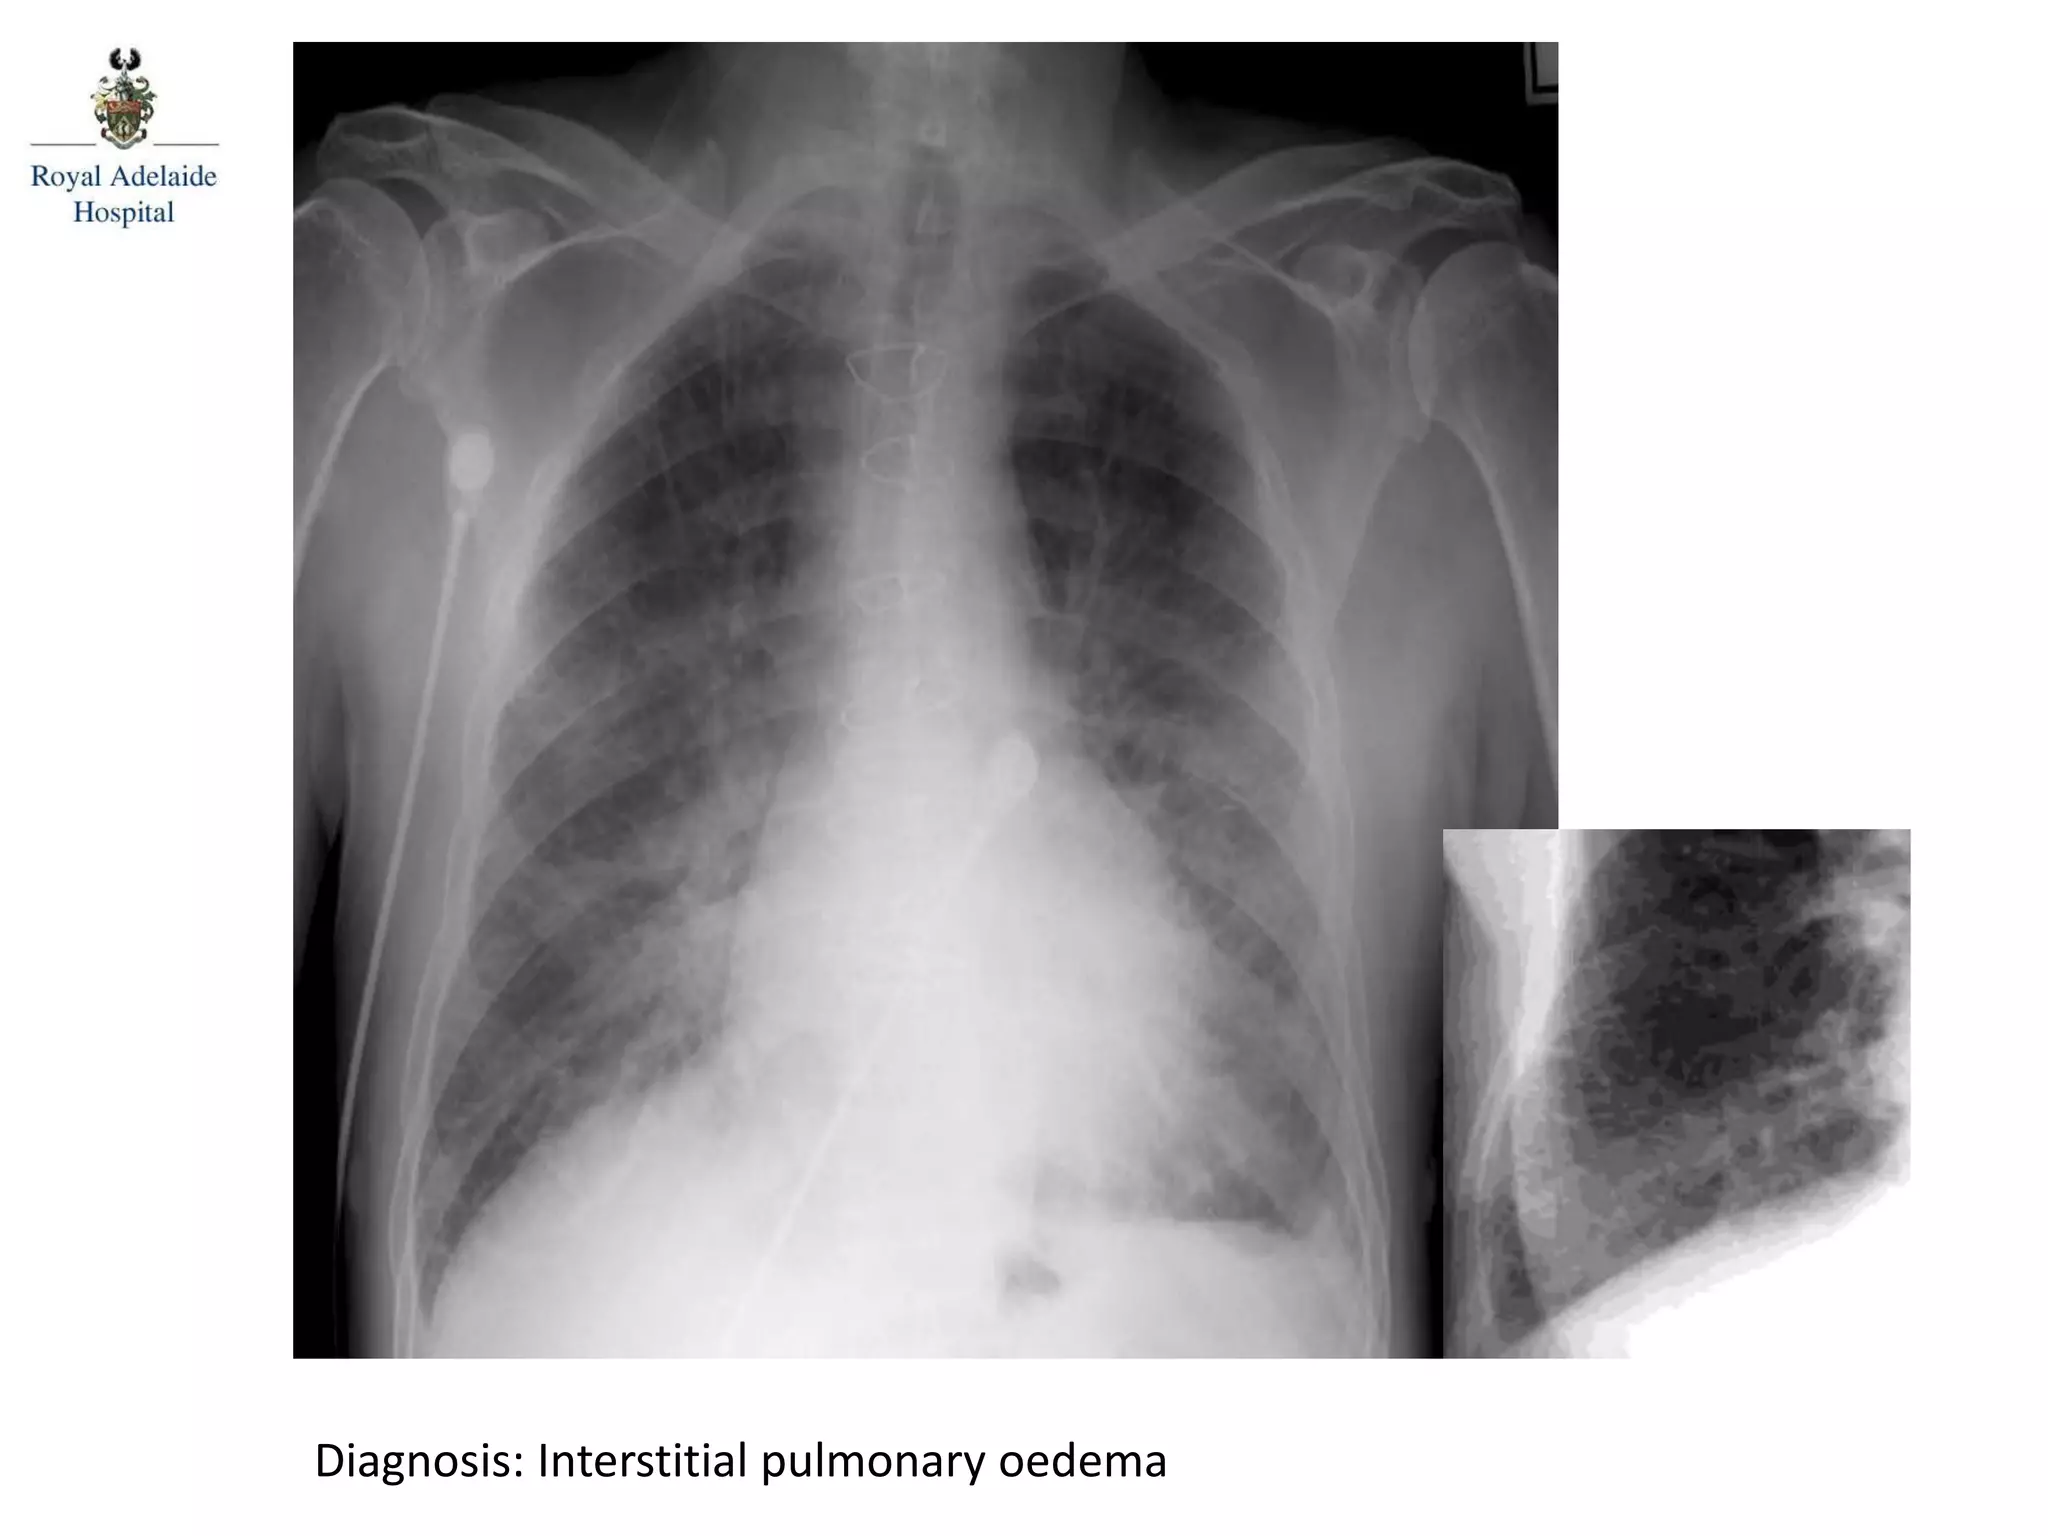

Diagnosis: Interstitial pulmonary oedema